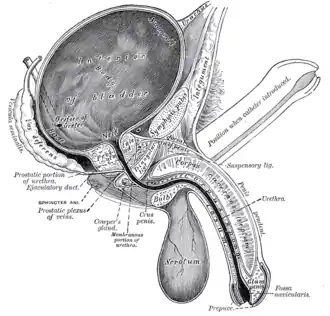

Vertical section of bladder, penis, and urethra. Urachus is seen at top | |

Urachus is #1 | |

The urachus forms from the distal end of the allantois in the embryo, and develops into a closed cord between the base of the bladder, and the navel.[1] It drains the bladder of the fetus that joins and runs within the umbilical cord.[2] The fibrous remnant lies in the space of Retzius, between the transverse fascia anteriorly and the peritoneum posteriorly. At birth, the urachus develops into the median umbilical ligament.[3][4]

The remainder of this part of the urogenital sinus forms the body of the bladder and part of the prostatic urethra. The apex of the bladder stretches and is connected to the umbilicus as a narrow canal. This canal is initially open, but later closes as the urachus goes on to definitively form the median umbilical ligament.